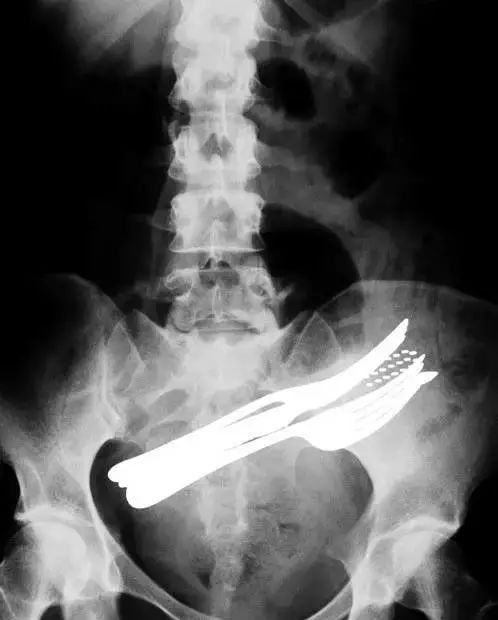

10、X射线图像显示这名患者吞下了包括叉子,牙刷和圆珠笔等异物: